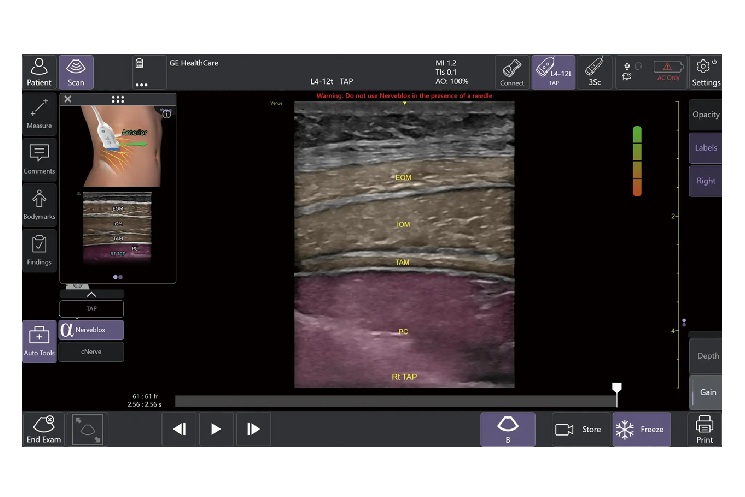

「Nerveblox」は、区域麻酔で使用される標準的な12種類の神経ブロック部位に対して、神経と、筋肉・血管・骨・筋膜などの周囲組織をリアルタイムに認識し、ハイライト表示する機能。麻酔科、救急科、集中治療科、整形外科などの診療科で、神経ブロック時の解剖学的構造の認識や視認性が向上し、よりスムーズな判断や手技の支援に役立つという。